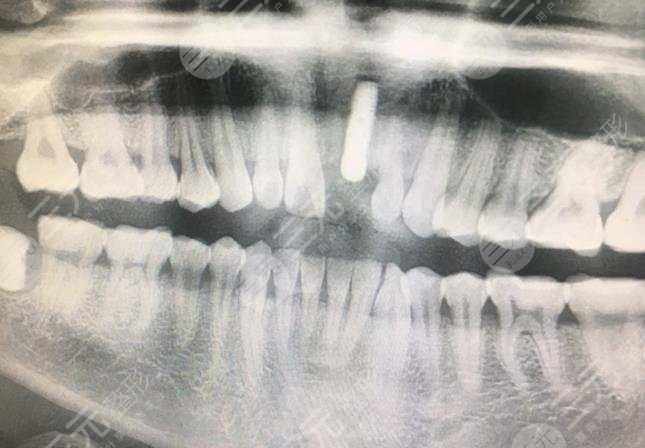

我是之前和朋友出去玩车的时候不小就把门牙磕掉了一半一直都没有补上,后来时间长了以后我就觉得这个门牙特别难看,主要是它还很影响我的生活,听很多朋友说可以通过种植牙手术来改善一下自己的牙齿情况,于是就去了医院打算看看,医生告诉我,我的情况的确也只有做种植牙了,因为已经没办法修复了,我去的是北大口腔医院,因为这里在种植牙手术领域里还是较为权威的,于是我就在朋友的陪同下来到了北大口腔医院。

在北大口腔医院做手术的时候,我还是有一些紧张的,但是能够感觉到这里的医生真的较为专业,有很多医生都是北京大学的教授呢,我在这里做牙齿种植手术的时候,手术操作是很快的大概一个小时左右就完成了,但是这个手术是要分几个步骤完成的,总共的时候是花了一个月,做完手术以后医生还告诉了我很多注意事项,总之我觉得这里的医生虽然很忙,但是较为负责任。